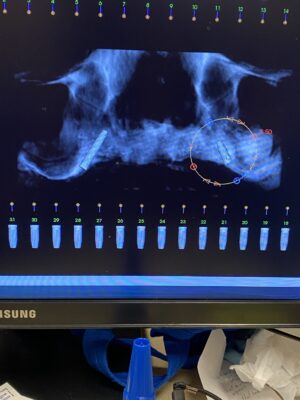

• I placed this implant 8 months ago. It was immediate placement. I did the uncovery today. The pre op radiograph shows some loose bone graft. I didn’t really notice anything off upon flapping . ISQ 77. Is it something I should be concerned about?

• So I suspect the implant was placed in cortical bone at the top and the lack of blood supply caused this die off. It could also be the lack of KT thickness. This is why I routinely place my implant 2mm subcrestal. At this point I don’t think there’s anything that can be done. It’ll be ok, just something to remember for next time.

• It doesn’t look like it will be a problem. Some of the graft turns over into natural bone–but some (like the graft stuck in soft tissue shown above your implant) will not turn over. It’s ok.